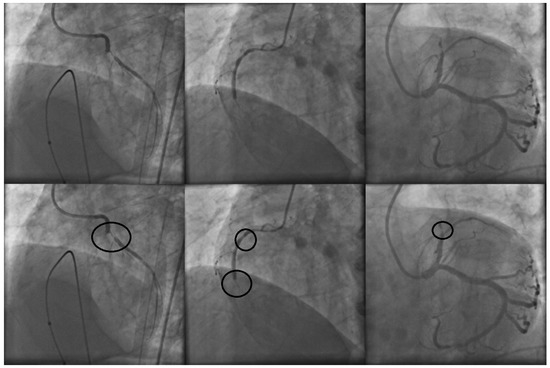

In clinical practice, stenosis detection is conducted by specialized cardiologists. To determine the presence of stenosis on a X-ray coronary angiogram, the specialist performs an exhaustive visual examination over the entire image or a set of continuous digital image sequences. By using their expert knowledge, the specialists are able to mark those regions over the coronary X-ray angiogram with high probabilities to contain stenosis cases. Figure 1 illustrates a set of three X-ray coronary angiograms and the regions with stenosis that were labeled by the specialist.

Figure 1.

X-ray coronary angiograms in the first row and their respective stenosis areas labeled by the specialist in the second row.